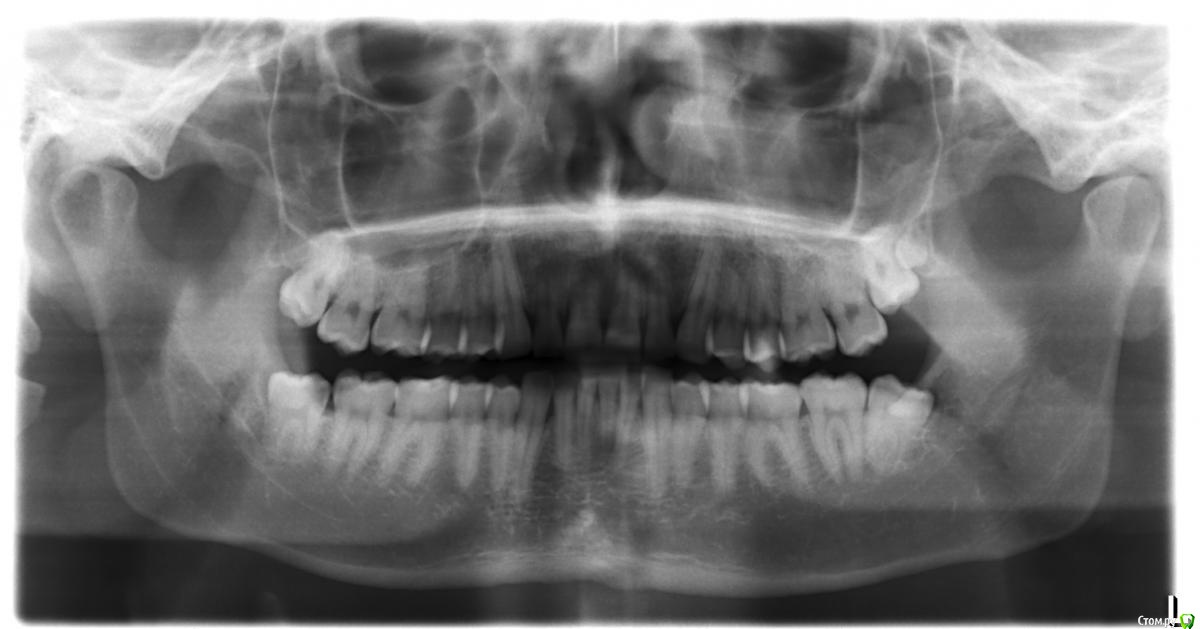

laz Опубликовано 31 мая, 2016 Поделиться Опубликовано 31 мая, 2016 Здравствуйте,Был на приеме у зубного врача, чтобы почистить зубы. Он сказал мне нужны пломбы на 4 зуба (1-7, 1-6, 2-7 2-6).Еще он сказал мне нужно удалить все зубы мудрости. (не обязательно сейчас, но в ближайщем будущем)Болей никаких у меня нет. Поэтому не знаю, как быть.Посмотрите, пожалуйста, на рентгены и очень хочу услышать Ваше мнение/совет.Заранее спасибо, Владимир. Ссылка на комментарий

red_butler Опубликовано 31 мая, 2016 Поделиться Опубликовано 31 мая, 2016 все правильно, удаляйте все восьмыеи девятый 5 Ссылка на комментарий

vse32 Опубликовано 1 июня, 2016 Поделиться Опубликовано 1 июня, 2016 и девятый Точно, 33! Ссылка на комментарий